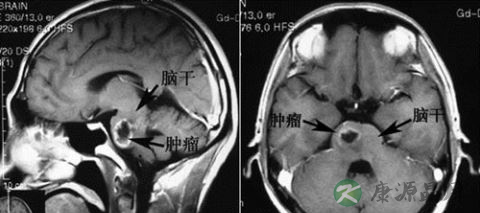

然而,全敏宇的脑瘤为脑干胶质瘤,利用手术切除恐造成死亡,只能靠放射性治疗,当时医生研判他仅剩6个月的寿命,他靠乐观积极的个性与病魔再对抗了1年多,2月9日凌晨在中国吉林老家延边的医院离世。

儿童肿瘤主要包括脑瘤、淋巴瘤、神经母细胞瘤、肝母细胞瘤,肾母细胞瘤等,这类疾病主要源自母体或基因缺陷。

大家熟知的白血病,约占儿童肿瘤的三成,剩下的是中枢系统肿瘤(脑瘤)和其他实体肿瘤。与成人肿瘤不同,儿童肿瘤进展极快,从一期发展到四期最快只要三个月。因此早期发现至关重要。